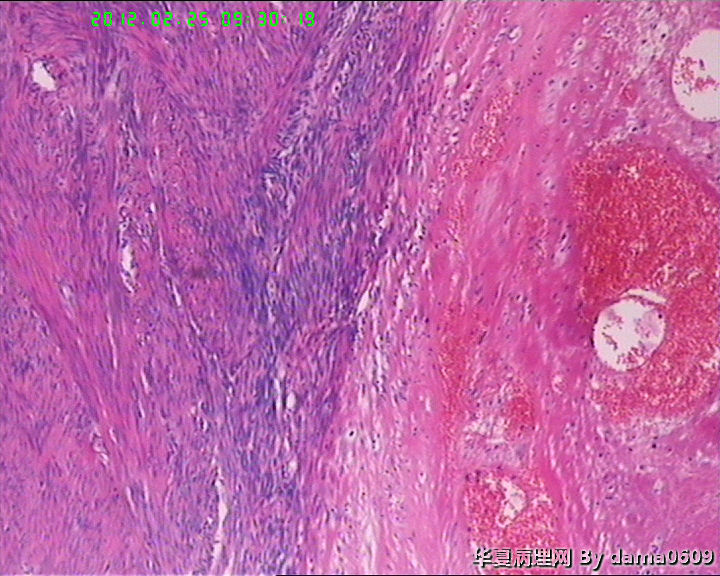

患者女性,48岁。临床未提供病史。

妇科以“子宫肌瘤”手术,术中子宫光滑、与周围无粘连。

追问患者家属病史,曾以药物治疗子宫肌瘤,具体情况不详。

巨检:次全切子宫,v:9.0x7.0x5.5cm,肌壁间见两枚肌瘤样结节,一直径0.6cm,无特殊;另一直径7.0cm,切面实性、质中、灰白、编织状、隆起、与周围肌层界限清。二者均呈典型平滑肌瘤外观。但体积大者,中心处局部见灰黄绿色坏死灶,直径约2.0cm,不规则,中间有点状红色区。

学生问题:1、这样的坏死在子宫平滑肌瘤中常见到,肉眼观界清,镜下坏死灶与周围正常组织陡然分界,无移行带,又不见明显炎细胞浸润,故怀疑是否为凝固性坏死??坏死灶内坏死平滑肌细胞无异形性,但轮廓清晰可辨,是否为“鬼影细胞”?

2、此例坏死灶周围平滑肌组织核分裂像很容易见到,时而一个高倍视野竟有四个,如何解释、诊断?再者学生对平滑肌细胞核分裂像也不肯定,请老师指教,应该不是核固缩。